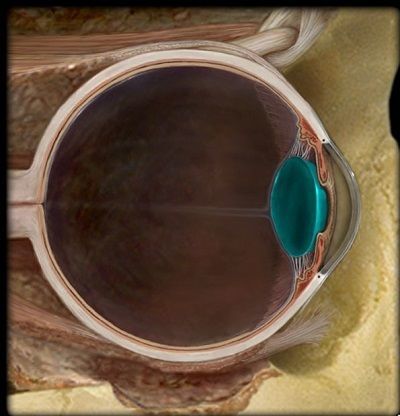

Question 2

Question

¿Qué estructura esta señalada?

Image:

6e29da6a-fbf8-411f-a7d1-e57dc5fdf895 (image/jpeg)

Answer

D. Optico

N. Optico

Iris

Conjuntiva

Macula